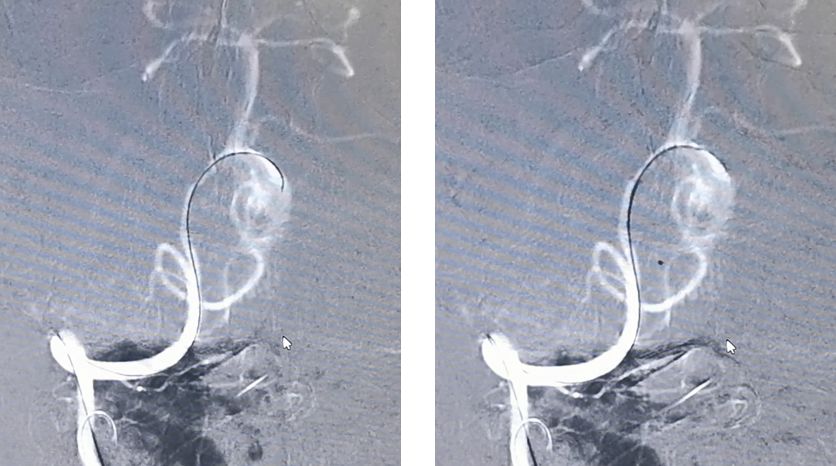

先用Synchro-200携Echelon-10由右椎动脉进入动脉瘤腔,微导管在瘤腔内盘圈,可以在输送弹簧圈的时候使弹簧圈分布更均匀

然后将Marksman微导管通过左侧椎动脉顺利进入左侧大脑后动脉

PED支架沿Marksman进入准备释放

释放PED。由于瘤颈很宽,所以PED需要足够长,动脉瘤远端和近端才能具有足够的锚定力量,防止支架坠入瘤腔内。所以,我们选择了3.25*35mm的支架。支架上端定位在基底动脉中段

PED释放完毕,位置及贴壁良好,左椎-基底动脉血运通畅,未填弹簧圈,即可见到瘤腔内造影剂的滞留,说明支架贴壁良好,起到了良好的重建作用

经右椎动脉逐步填塞大弹簧圈进入动脉瘤(Microplex-18系列),逐步将动脉瘤疏松填塞。期间微导管头端受到弹簧圈阻力,会缓慢回撤,此时不必刻意调整微导管再次深入动脉瘤腔内,因为我们最主要目的不是严密填塞动脉瘤—那是PED的任务—而是闭塞右侧椎动脉

最后,用小弹簧圈完全闭塞右侧椎动脉(PICA以远)